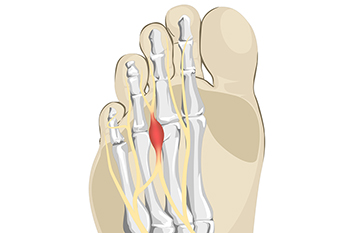

Do You Feel Like You Are Walking on a Pebble? When the nerve located between the third and fourth toes becomes compressed or otherwise irritated, the tissue surrounding it can thicken and become inflamed. This condition is known as Morton’s neuroma, or intermetatarsal...